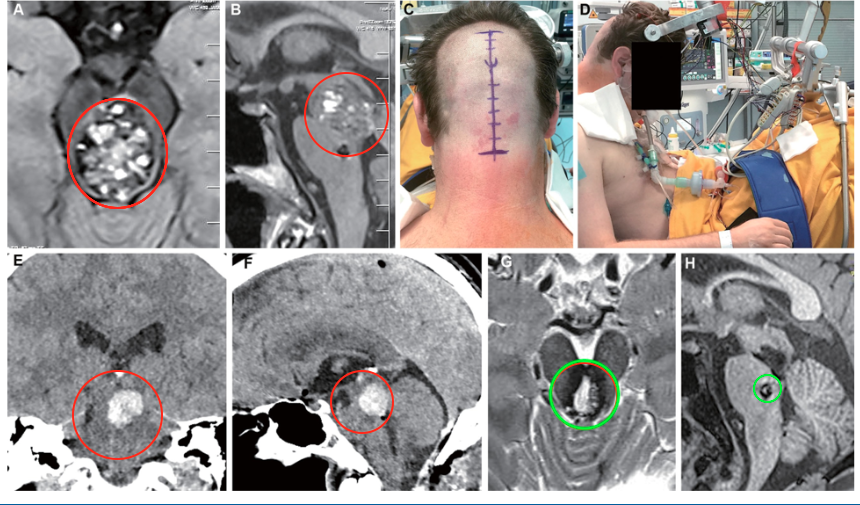

术前情况:术后早期出血,影像显示中脑部位分布着一些小的海绵状血管瘤(A、B为术前影像)

手术体位:半坐位

手术入路:枕骨下入路

术后情况:E图为冠状动脉,F矢状位CT重建显示了切除腔内术后早期占位性血肿。G、H为手术后5个月的影像学检查,显示完全去除了血管畸形病变。